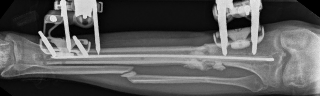

Nail Insertion and Distal Interlocking

Following meticulous preparation, the canal is reamed sequentially. Care must be taken not to over-ream the distal segment, which could compromise the already tenuous metaphyseal bone stock. The nail is inserted gently; forceful impaction is strictly avoided to prevent displacing the previously secured articular block.

Image

Distal interlocking must be maximized. The surgeon should utilize a minimum of three, and ideally four, distal locking screws, engaging the bone in multiple planes (e.g., two medial-to-lateral, one anterior-to-posterior). This multi-planar fixation is essential to control rotation and angular displacement in the wide metaphyseal bone.